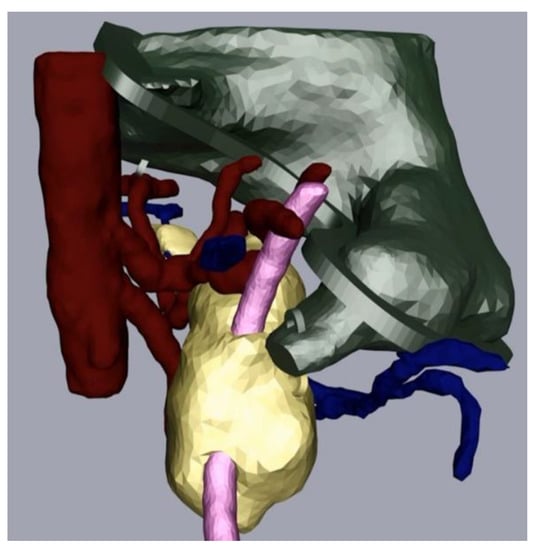

The next part of the process was the mesh refinement as described above. For this, we smoothed the mesh with the program Meshmixer (Step 3a) and added hooks to be able to join the physical replica parts together with strings later. We also performed additional processing in Cinema 4D (Step 4). In our case, this consisted of adding a flange as we wanted to be able to open and close the stomach. We made a video that displayed the different parts of the replica coming together (available on request). Figure 4 depicts the assembly after processing and before the last level of 3D printing.

Figure 4.

Pancreas (yellow), arteries (red) veins (blue), stomach with flange and hooks (green) and splint (pink) after processing.